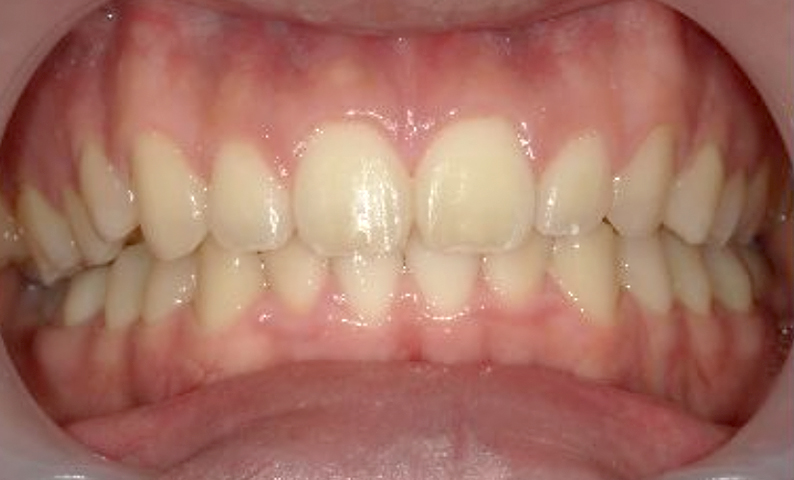

| 治療前 | 治療後 |

|---|---|

|